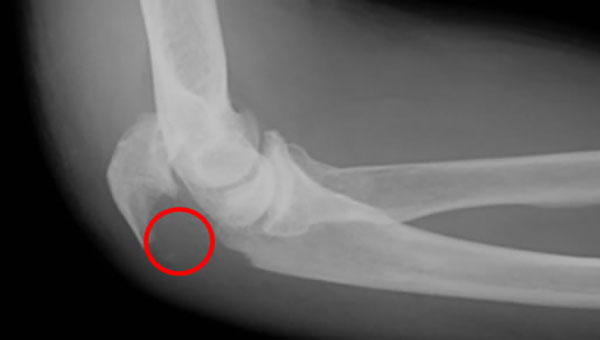

肘頭骨折は、肘周辺の骨折の中で比較的頻度の高い関節内部の骨折です。

肘頭とは、尺骨の近位端部にある丸みを帯びた突出部のことです。一般に「肘鉄」などと

呼ばれる肘の頂点の部分です。肘頭骨折は、この部分に外力が加わることで生じます。

また、肘頭は、上腕三頭筋により上方へ引っ張られているので、これが骨折すると、骨がずれて転位が生じます。下のイラストのとおりです。

肘頭部を骨折すると痛みや腫れが生じ、肘の可動域制限と異常可動がみられます。単純XP撮影でも容易に骨折を確認できます。